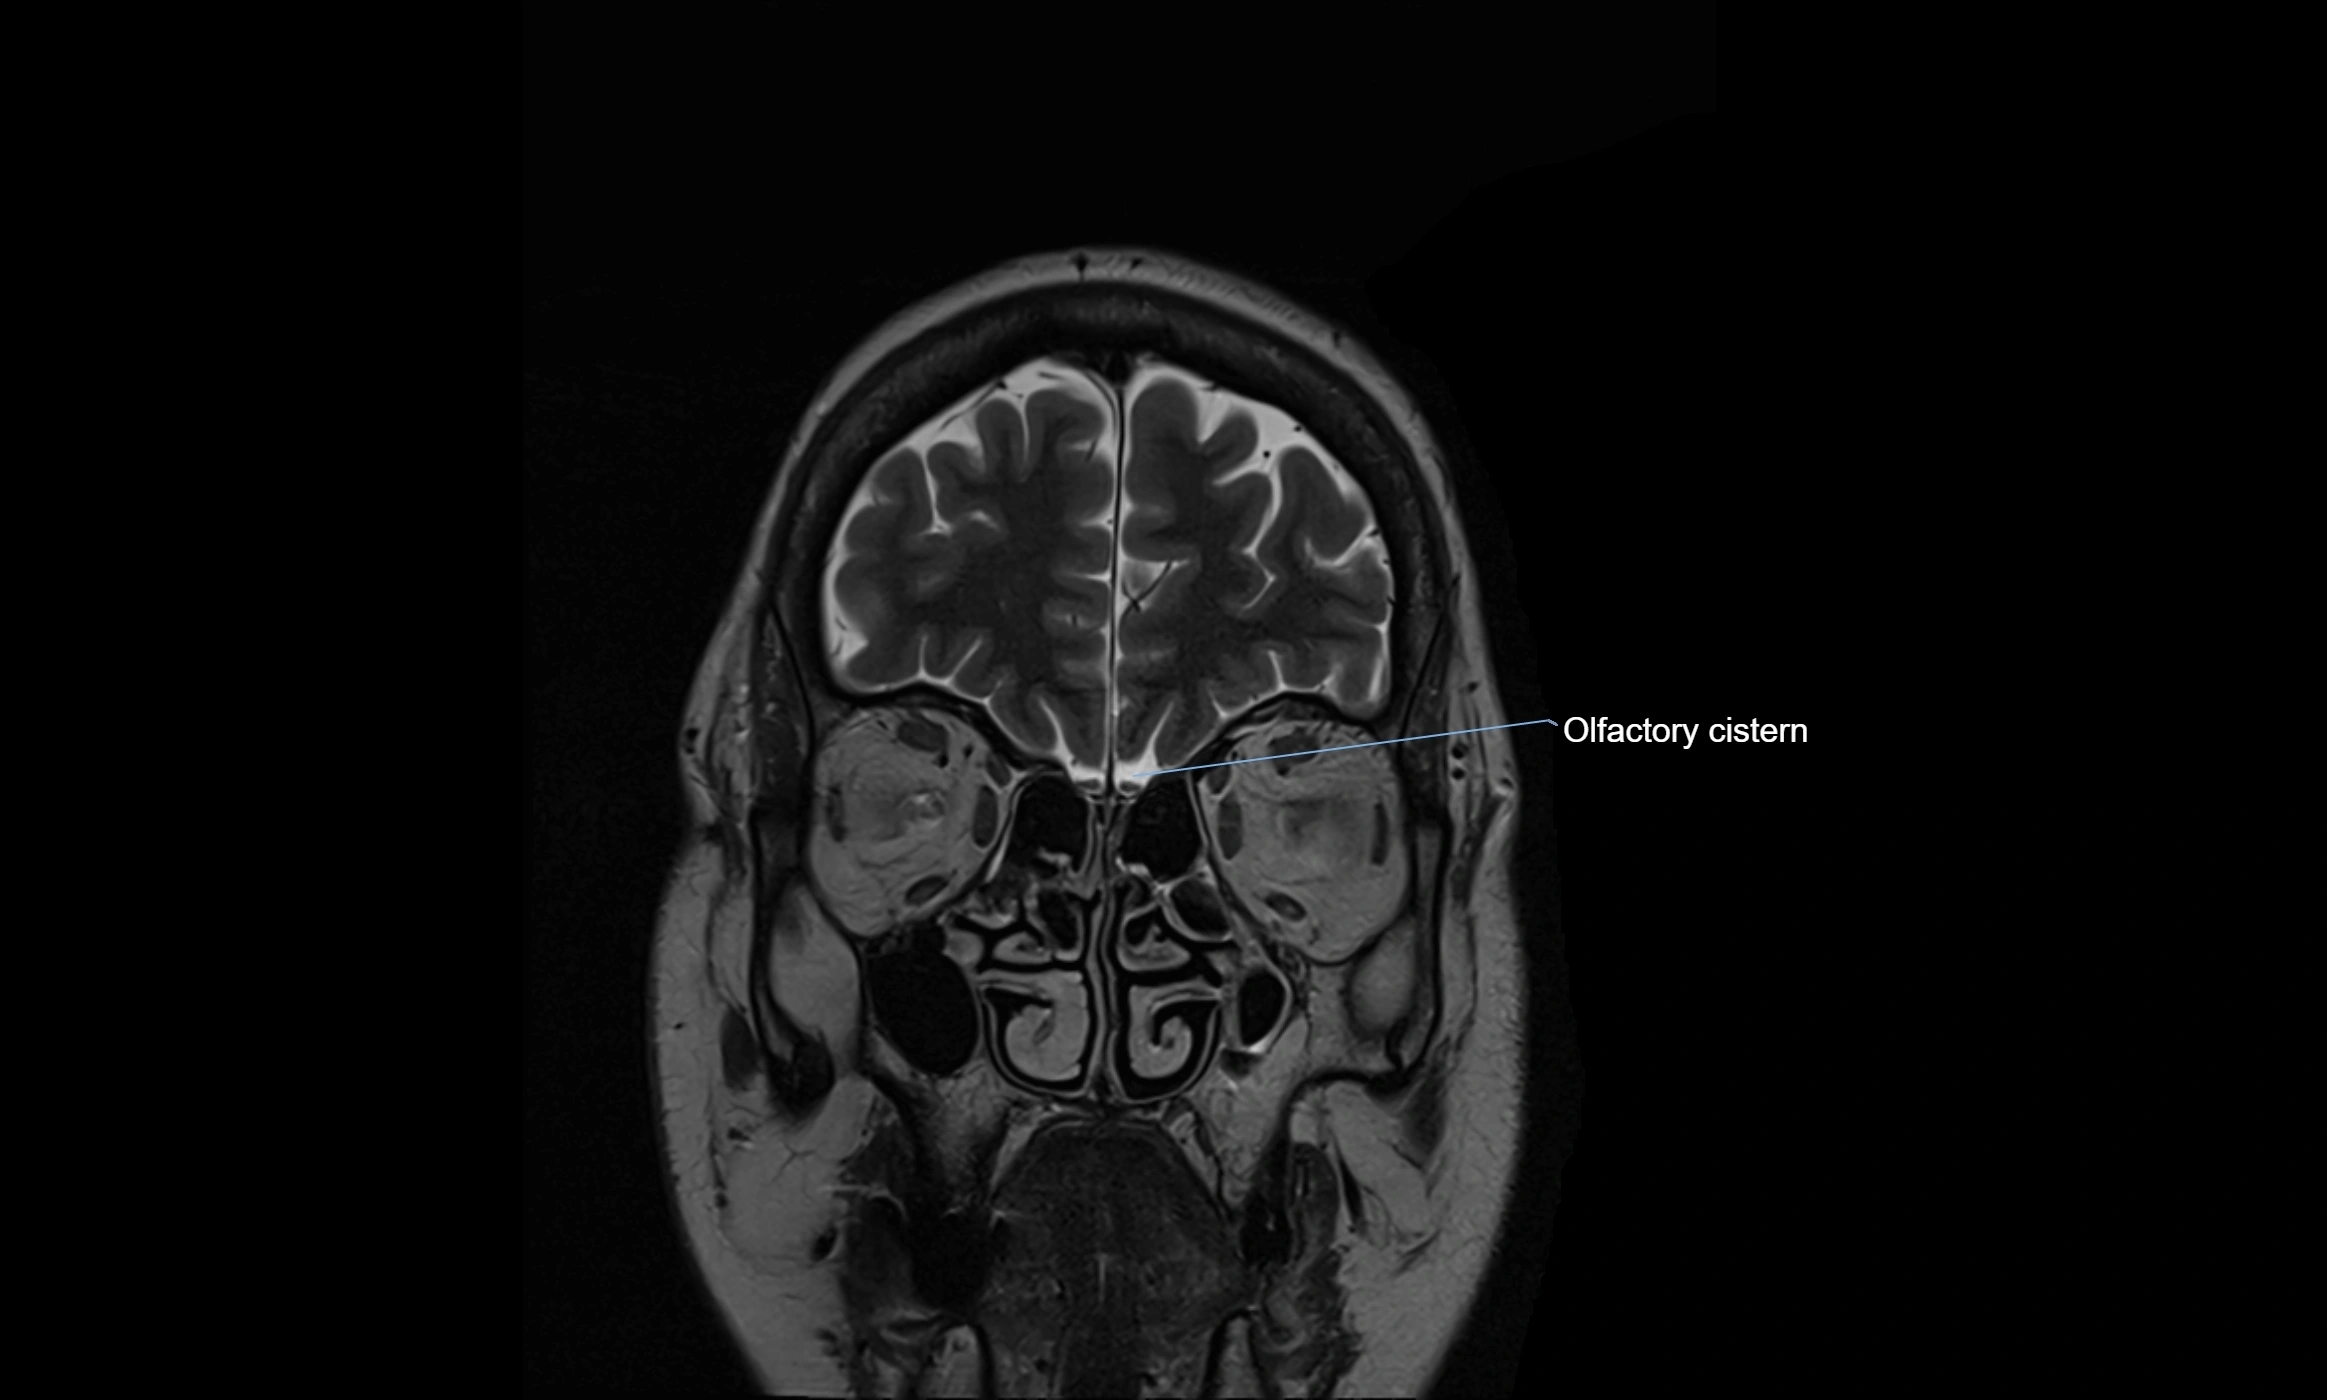

MRI images

image